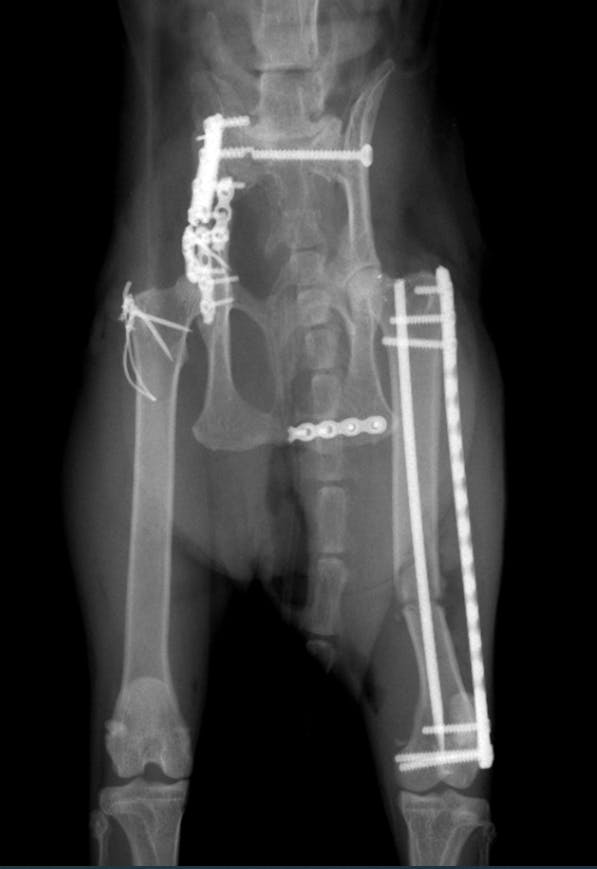

チタンプレートで固定する手術になります。

骨折治療箇所は6箇所(しっぽも骨折しておりましたがこちらは治療いたしません)

このように腸骨の復元とチタンプレート固定で骨を正しい位置に修正します。

左脚の大腿骨遠位端成長板分離骨折

左側の腸骨骨折部の固定

両側の仙骨脱臼の整復

仙骨脱臼により骨盤が狭窄された形になり、重大な排便困難になる可能性が高いのでその治癒を目的とした治療です。

固定した腸骨の上端をボルトやワイヤーで内側に引っ張ることで仙骨を支点にして骨盤内腔を拡げます。